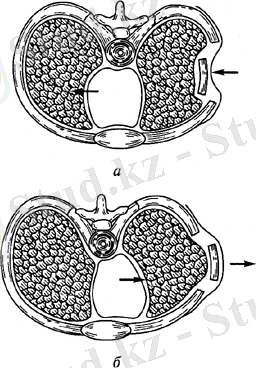

Оконч Сынықтарда кеуде қуысының қалпы бұзылады. Дем алу кезінде, бірнеше қабырғалардың екі еселенгген сынықтардан түзілген (қабырғалық клапан) қозғалмалы сегмент ішке тартылады, ал дем шығарған кезде, кеуде қуысының көлемінен тыс шығады. Оконч сынықтарда, науқастың ауыр жағдайы қабырғалық клапанның флотирленген қозғалысынан болған тыныс алу бұзылысы мен байланысты, ол парадоксальды тыныс алуды шақырады. Зақымданған жақтағы өкпе көлемінде дем шығару кезінде басқа өкпеден ауаның түсуі әсерінен ұлғаюы парадоксальдықты негіздейді. Дем алу кезінде, оконч сынықтың ішке қарай, түсуінде өкпе көлемінде кішірейеді және ауа одан қарама қарсы жаққа ( сау жақ ) ұмтылады. Бұл жағдай қабырғалық «терезе» қозғалысының көкет аралықтың ығысуының бірігуімен қиындай түседі. Мұндай тыныс алу өкпе - жүректік жетіспеушілік, плевропульмональді шок дамуына әкеледі.

Сурет1. Қабырғалардың оконч сынығы кезінде көкет аралықтың және қабырғалалық клапанның ығысуы.

А-дем алу кезінде, б-дем шығару кезінде. .